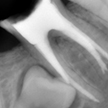

2. 初診時右下6番X線デンタル

初診時の主訴であった右下6番の歯冠が脱離した部位のX線デンタルです。患者様は銀歯が脱離してしばらく放置したとのことで、痛みもないので又歯冠をつければ良い位に考えていた様子でした。歯根吸収の状況より当時22歳とのことで、相当若年時に抜髄されたのが想像できます。考えてみれば6歳に萌出して15年で抜歯となった訳です。上顎8番の同部への移植も考慮しましたが断念しました。